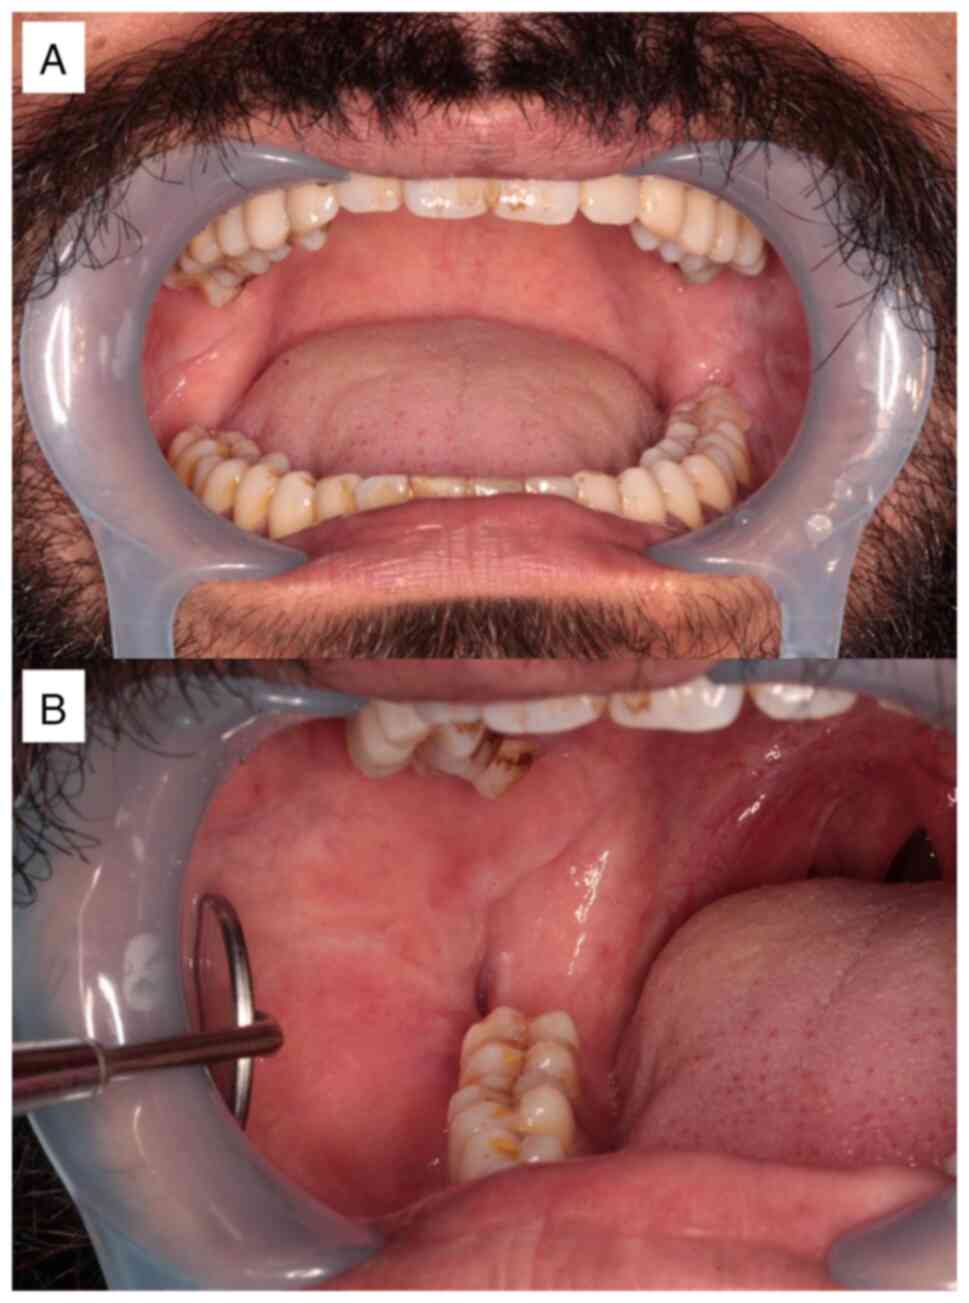

showed that all cysts were removed (Fig. 1C). At the time of their first visit

to the University of the Ryukyus Hospital, an intraoral examination

showed that the buccal gingiva corresponding to the lower right

wisdom tooth was depressed owing to previous surgery (Fig. 2A and B). Panoramic radiographic examination